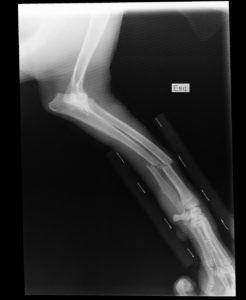

invaliditet